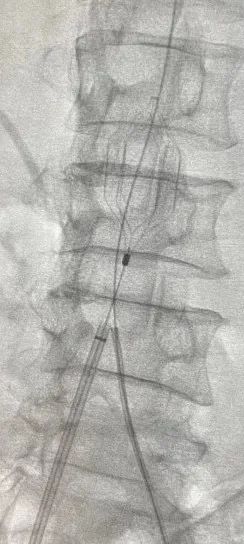

▲术中血栓保护

(血栓抽吸过程)